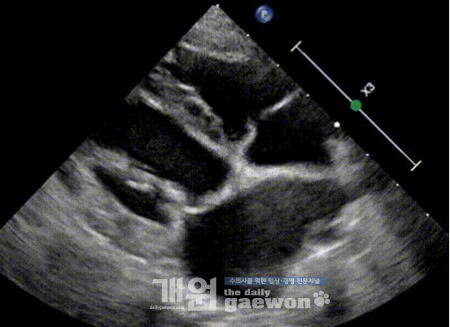

해당 환자는 8세, 6.2kg의 스피츠로 단백소실성장병증(Protein-Losing Enteropathy, PLE)을 앓고 있었으며, 장기 항생제 치료 이력이 있는 고위험 환자였다. 1차 수술에서는 점액종성 변화로 변성된 판막을 재건해 역류를 현저히 개선했고, 이후 약물 없이 안정적인 회복을 보였다. 하지만 수술 약 4주 후 판막에 세균 감염이 발생했고, 정밀 검사 결과 다제내성균인 엔테로코커스 페시움(Enterococcus faecium)에 의한 감염성 심내막염으로 확인, 장기 항생제 치료와 장염으로 인한 장벽 손상이 원인으로 지목됐다. 의료진은 6주간 정맥 항생제 치료로 감염을 통제했지만 판막 구조 손상이 심각해 재수술이 결정됐다.

2차 수술에서는 감염으로 짧아진 승모판막 전엽을 소 심낭 패치로 연장하고 재건하는 전엽 패치 증강술(anterior mitral valve leaflet patch augmentation)을 적용했다. 이는 사람 심장 수술에서 활용되는 고난도 기법으로 개에게 적용된 것은 처음이다. 9시간에 걸친 수술 이후 환자는 모든 심장약과 이뇨제를 중단할 수 있었고, 재수술 3개월이 지난 현재까지 기절 증상 없이 정상적인 생활을 이어가고 있다. 감염성 심내막염을 앓은 개의 평균 생존 기간이 약 70일인 점을 고려하면, 발병 후 10개월 이상 생존하며 호전 중인 이번 사례는 수술적 치료의 가능성을 입증한 중요한 사례로 평가된다.